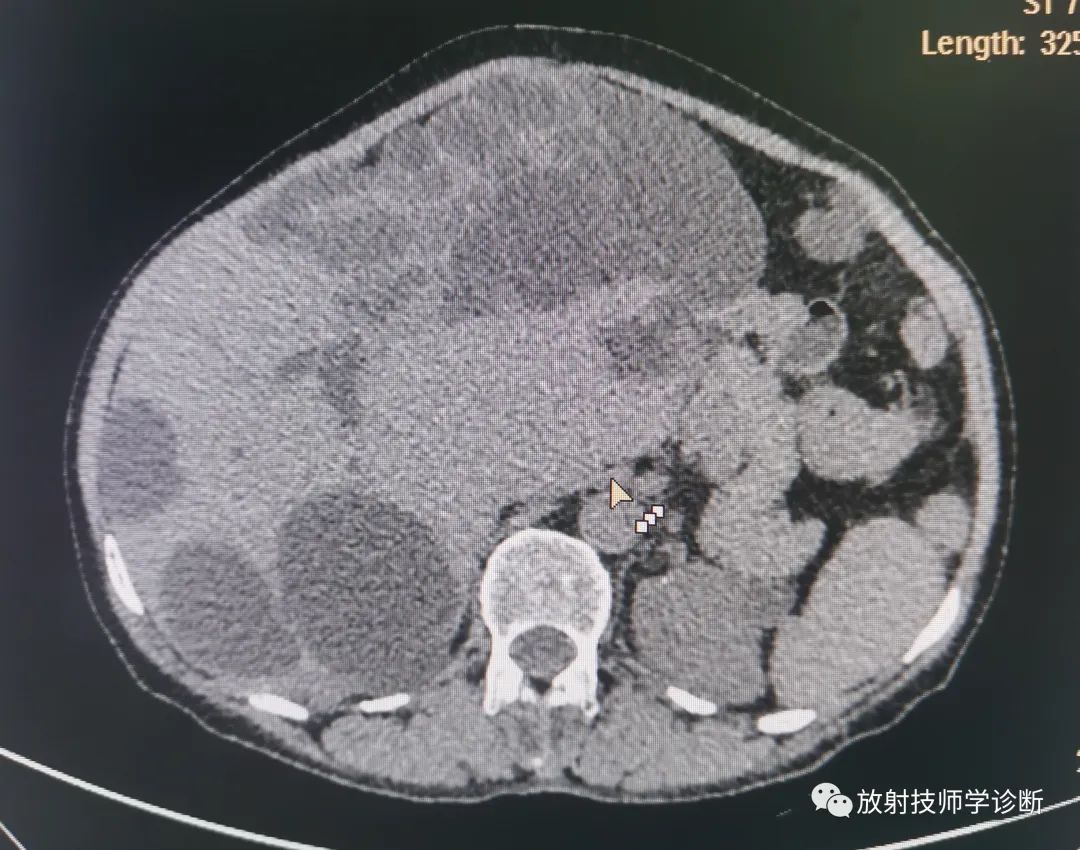

典型多囊肝

多囊肝,是一种常染色体显性遗传病,表现为肝脏的多发性弥漫损害,囊肿间的肝细胞正常,多合并多囊肾,同时在胰腺、脾脏、双肺及女性卵巢可发现囊性病变。多囊肝合并多囊肾致病基因位于人第16对常染色体上,DNA分析可作为疾病无症状时和产前的早期诊断。

(2)CT检查:可明确囊肿的大小、数目、解剖位置,并可发现1~2cm肝囊肿。CT平扫表现为肝内弥漫大小不一的水样低密度影,边缘光滑清楚,CT增强后无强化。

图片